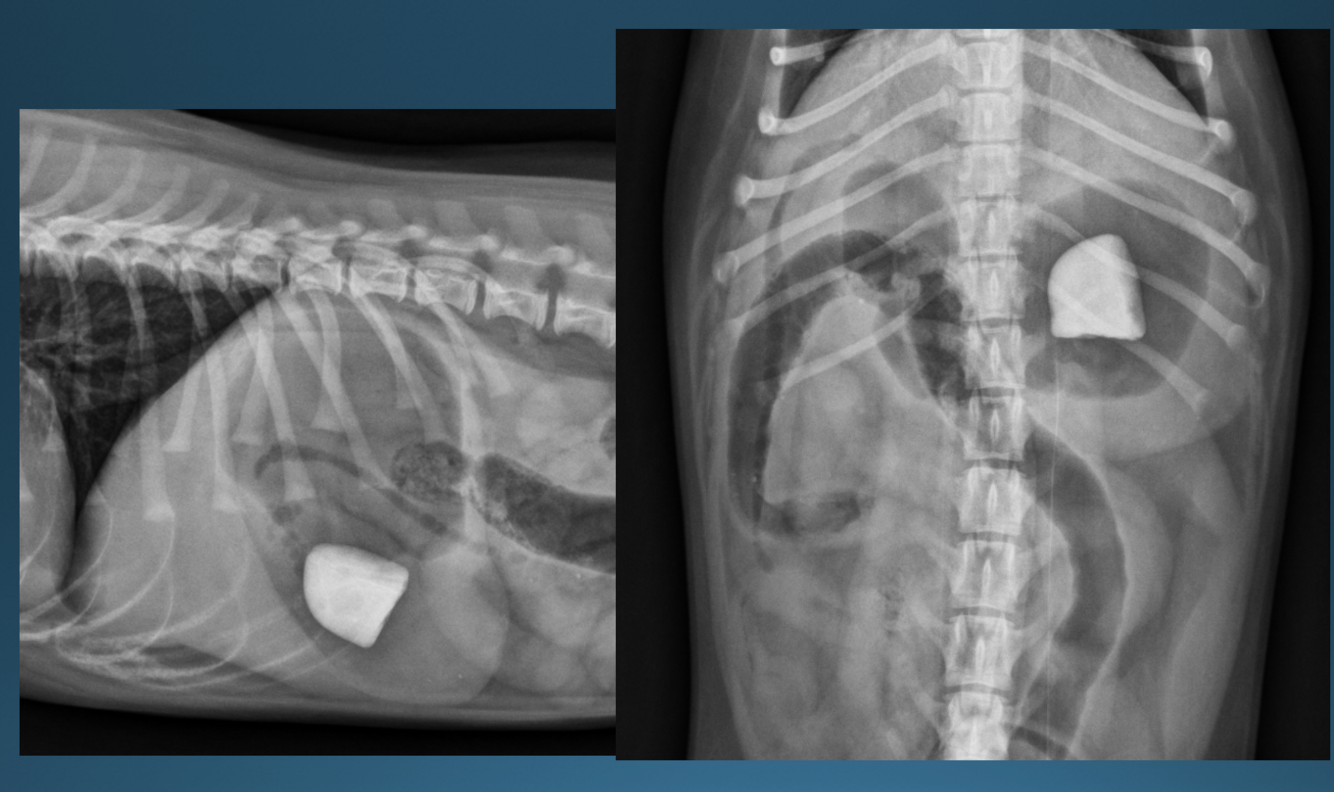

Q

A

canine gastric foreign body

-rock

-within fundus; can move and block pylorus